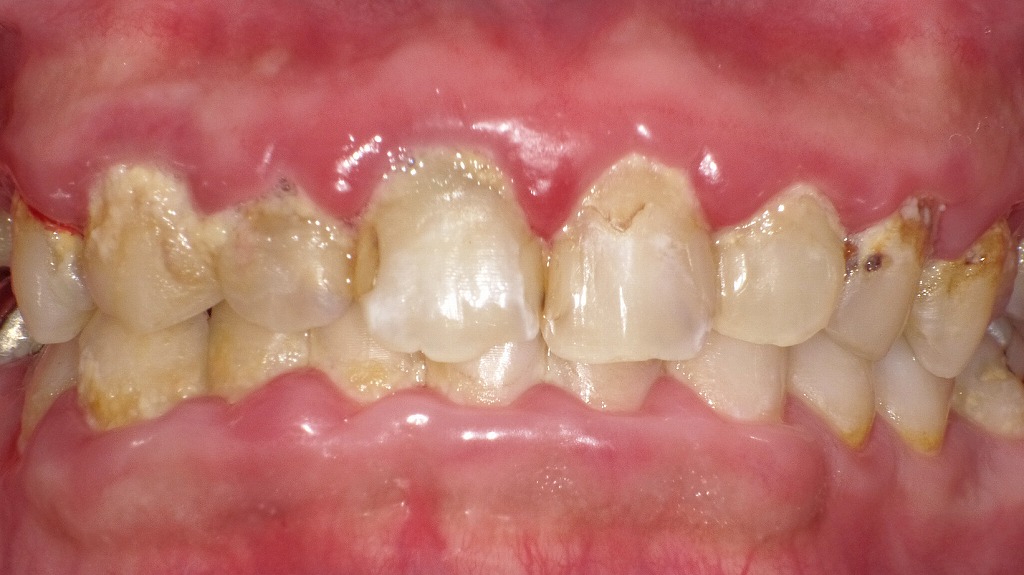

歯周病が進む口の中|磨き残しと歯石がもたらすサイン

この写真では、上・下の前歯周囲に大量のプラーク(歯の表面に付着した細菌のかたまり)と歯石が確認されます。歯ぐきは全体的に赤く腫れ、丸く膨らんだ炎症状態で、これは典型的な**歯周病**の所見です。

特に以下の点が歯周病の進行を示しています:

- 歯と歯ぐきの境目に厚く付着したプラーク・歯石

ブラッシング不足が続くと、柔らかいプラークが硬くなり歯石となり、歯周病菌の温床になります。 - 歯ぐきの赤み・腫れ・丸み

健康な歯ぐきは薄いピンク色で引き締まっていますが、炎症があると赤く腫れて丸く盛り上がります。 - 一部に虫歯による黒っぽい変色や歯面のざらつき

細菌の増殖と虫歯、歯石沈着によるものです。

この状態では適切な歯磨きだけでは改善が難しく、歯科医院での歯石除去(スケーリング)と専門的な歯周病治療が必要となります。